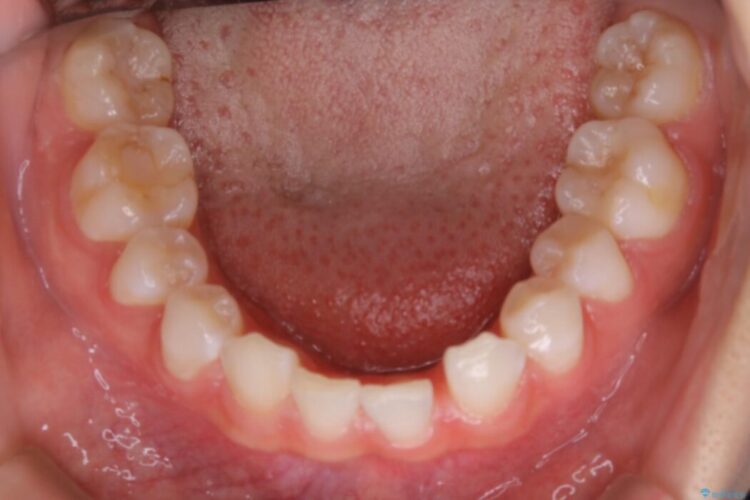

診査したところ叢生だけでなく生まれつき永久歯の欠損、いわゆる先天欠如により歯の本数が少ないため噛み合わせなどにも影響が出ている状態でした。

特殊な状況からの矯正治療となるため、抜歯する本数や位置、歯列を整えるにあたって必要なスペースの確保を慎重に計画し、インビザライン コンプリヘンシブパッケージでのマウスピース矯正を行いました。